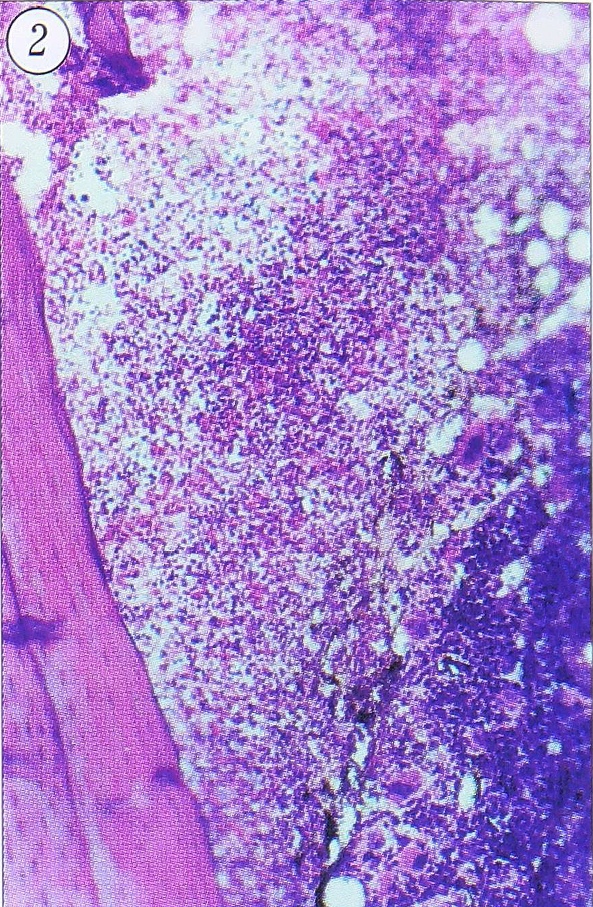

Строение очагов остеомиелита в острой и хронической стадии. В острой стадии ТО после остеотомии с инфицированием у крыс поражение не носит характера четко очерченного очага, так как еще не завершено формирование капсулы. В центре располагается обширная зона некроза костного мозга, по краю которой наблюдается картина серозно-гнойного воспаления (рис. 1, 2), а к 7-м суткам краевые отделы некротизированного участка костного мозга находятся в состоянии гнойного расплавления. Через 2-3 сут после начала острого инфекционного воспаления, кроме альтеративно-экссудативных и деструктивных изменений, в реактивной зоне начинается пролиферация незрелых клеток: фибробластов, остеобластов, эндотелиоцитов, миобластов (в пароссальных мягких тканях) и др. Ширина этой зоны в сроки 3—7 сут увеличивается. Через неделю после травмы идет активный рост грануляционной ткани, которая может длительно сохраняться в очаге в виде внутренней оболочки капсулы остеомиелитического очага, в то время как внешние отделы грануляционной ткани, созревая, образуют фиброзную оболочку.

Рис. 2. Серозно-гнойное воспаление при остром травматическом остеомиелите большеберцовой кости крысы. Срок 3 сут. Ув. 80.